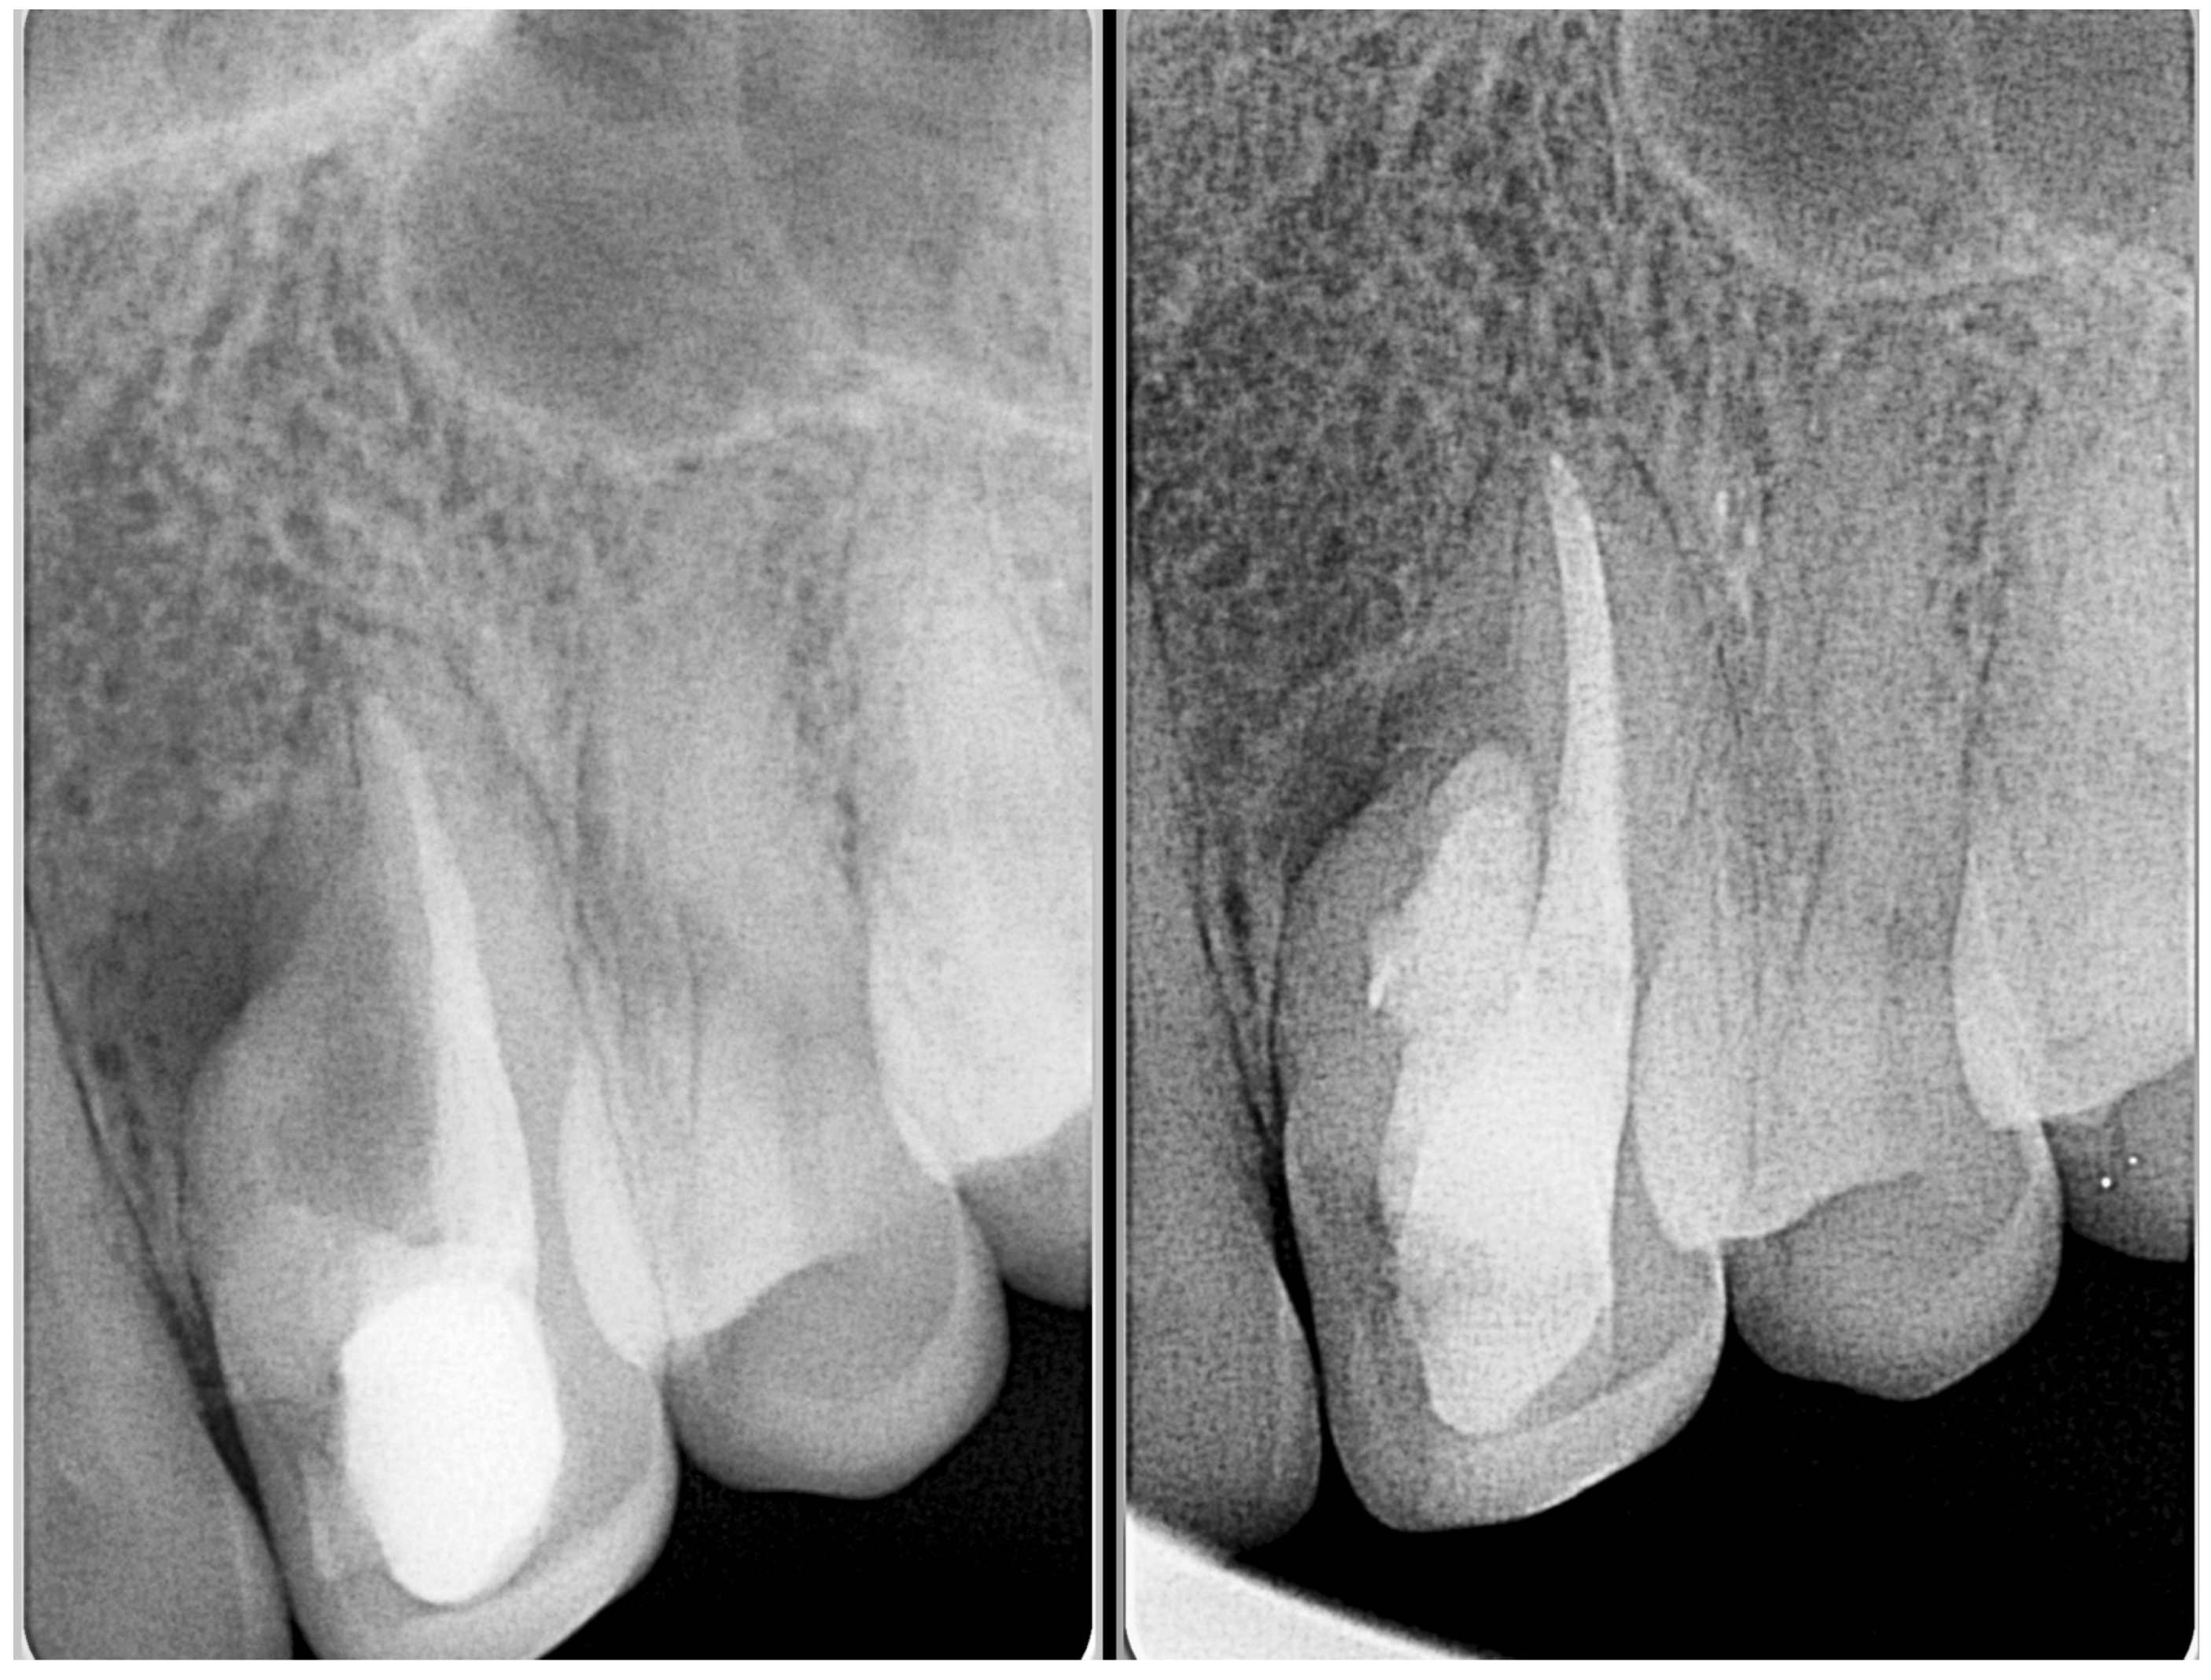

- Gonçalves, A.; Gonçalves, M.; Oliveira, D.P.; Goncalves, N. Dens invaginatus type III: Report of a case and 10-year radiographic follow-up. Int. Endod. J. 2002, 35, 873–879. [Google Scholar] [CrossRef] [PubMed]

| Type IIIa/IIIb | High risk of periapical/periodontal infection | CBCT essential to determine anatomy and extent | Selective treatment of infected invagination if pulp unaffected Often requires surgical access and debridement Orthograde or retrograde obturation with biocompatible materials Combined endodontic and periodontal approach in complex cases | Prognosis depends on anatomical complexity and extent of infection Long-term monitoring essential due to risk of reinfection |